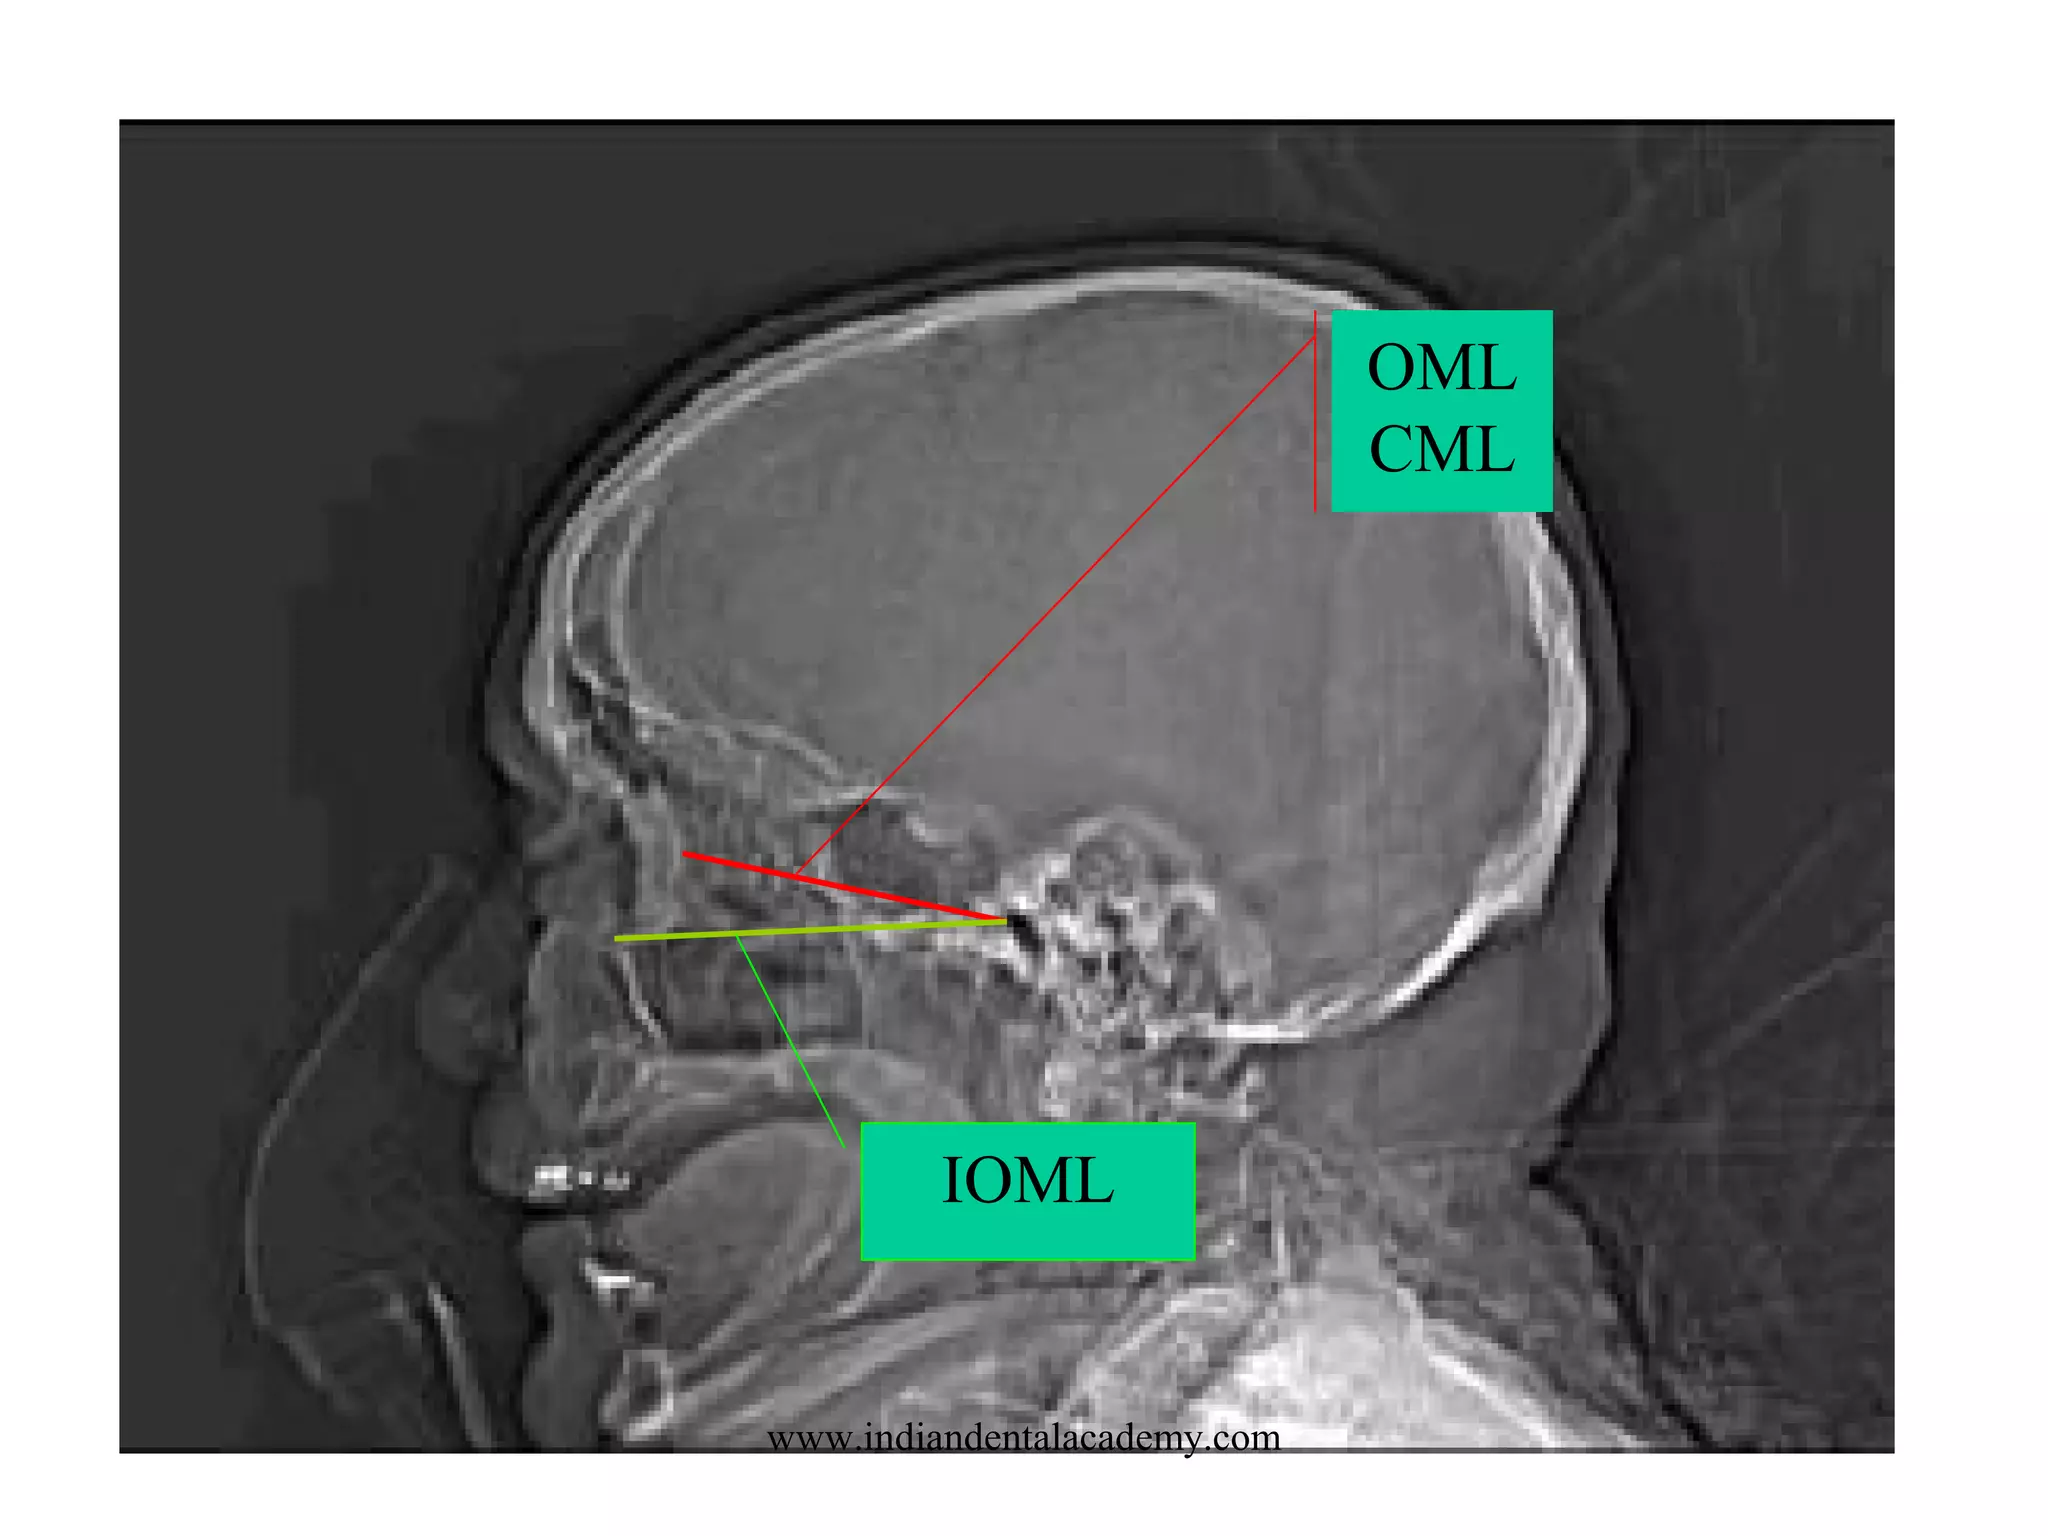

OML

CML

IOML

www.indiandentalacademy.com